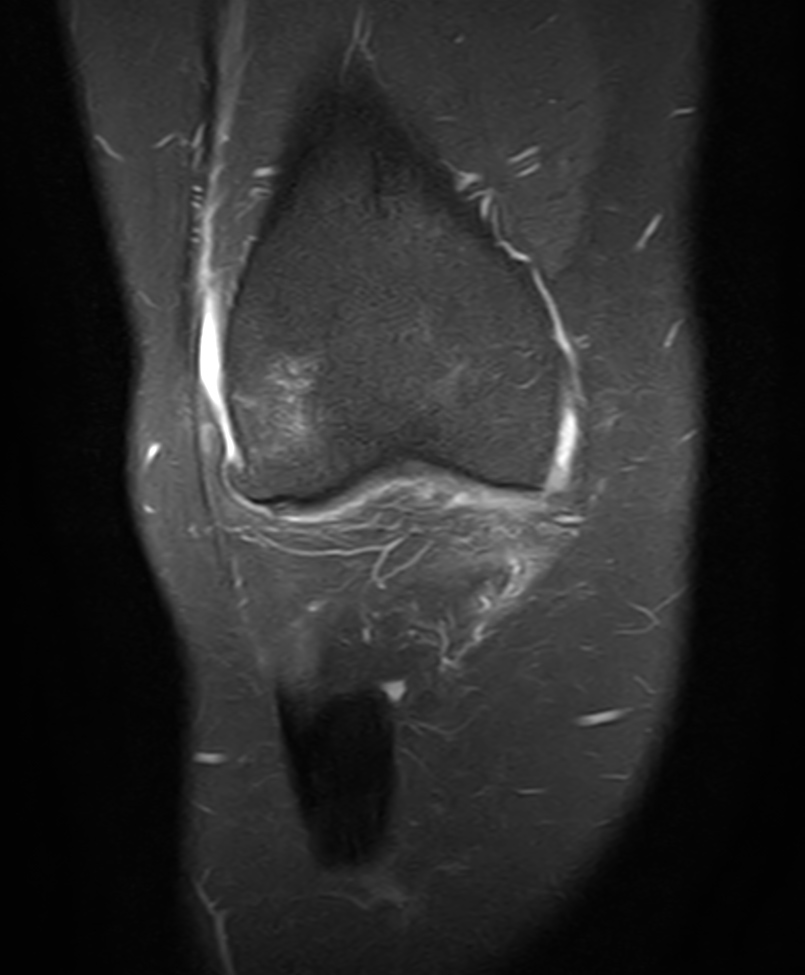

Coronal PDw SPIR